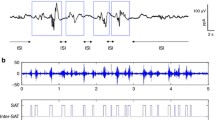

The second type of EEG features was event-based EEG measures related to the continuity of the signal: the burst percentage or SAT% and the median interburst interval (IBI) duration. The SAT events are detected using the algorithm proposed by Palmu et al. [23]. This algorithm applies the nonlinear energy operator (NLEO) to the bandpass-filtered EEG time series. A threshold was then applied on the smoothed absolute value of the output of NLEO to identify the location of the SATs. Subsequently, the SAT percentage among the complete recording, the average SAT percentage in non-overlapping windows of 5 min, and the median IBI length among the complete EEG recording were computed. Fig. 2 illustrates the NLEO-based detection of SAT events and interburst intervals on a 5-min EEG segment.

Illustration of the detection of spontaneous activity transient and interburst intervals in the preterm EEG. At the bottom, a 5-min EEG segment and the output of the NLEO-based SAT detection algorithm are presented. On top, a 30-s excerpt of the 5 min EEG segment is shown with labeled SAT events and IBI periods